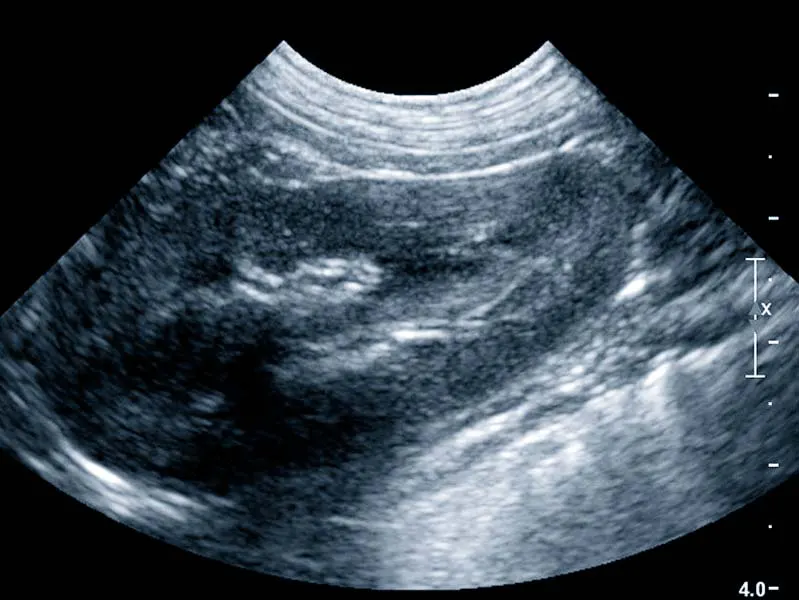

Ultrazvučna pretraga je važan dijagnostički alat u veterinarskoj medicini jer omogućuje veterinarima da dobiju detaljan uvid u unutarnje strukture tijela bez potrebe za invazivnim postupcima.

Tijekom ultrazvučne pretrage dio tijela je izložen bezopasnim, visokofrekventnim zvučnim valovima kako bi stvorio slike unutarnjih struktura tijela na ekranu uređaja.

Tako uživo možemo vidjeti kretanje, funkciju i strukturu unutarnjih organa vašeg ljubimca.

UZV se koristi u svrhu dijagnostike bolesti svih organa trbušne šupljine, srca i krvožilnog sustava.